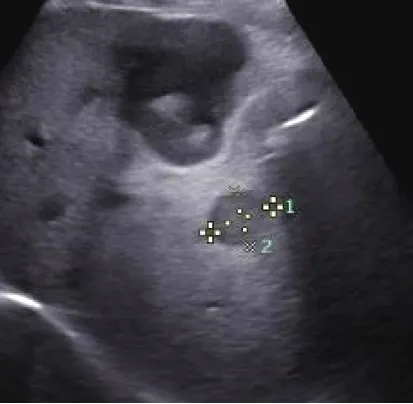

03

转移性肝癌

定义

● 是肝内最常见的继发性肝恶性肿瘤。

● 来源:转移性肝癌多来自于腹腔内肿瘤约占2/3,包括食管、胃肠道、胆囊、胰腺等消化系统恶性肿瘤居多。

● 不合并肝硬化。

病理特点:

瘤体快速增长,边缘瘤组织往往保持活跃的细胞生长结节内部,尤其瘤体中央区或中心发生不同程度缺血造成慢性组织变性、点片状坏死等不均质改变,伴随反复组织修复和结缔组织增生,有的发生液化坏死。

超声表现

● 圆形或椭圆形。

● 常多发,也可单发,在较大的转移性肝癌中可出现多结节相互融合,形似“葡萄串征。

● 内部回声多样,周边低回声的声晕(较宽)。

● 极少合并肝硬化。

● 少血供。

超声特点

● 牛眼征:有较宽的低回声晕,形似牛眼多见于腺癌肝转移。

● 高回声:多见于消化道恶性肿瘤。

● 低回声:常见于乳腺癌等。

● 囊性变型:多见于胃肠间质肉瘤、卵巢囊腺癌等。